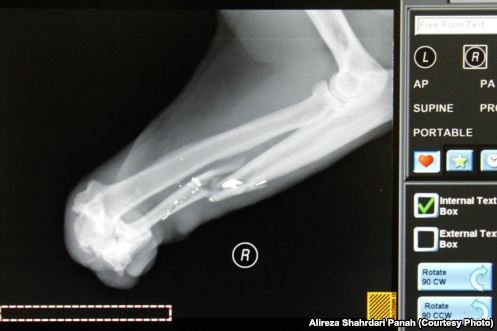

وی میافزاید: «همچنین دست راست حیوان به دلیل گیر گردن در تله مدتها پیش از ناحیه مچ قطع شده است. یکی از گلولههایی که به تازگی به حیوان شلیک شده بود کاملا در مجاورت مهره ششم کمری در کانال نخاعی دیده میشد. سی تی اسکن نیز نشان داد که گلوله از بدنه مهره پنجم کمری وارد کانال نخاعی شده و تا انتهای مهره ششم در کانال نخاعی حرکت کرده و کل کانال را پرکرده است.»

دست راست حیوان به دلیل گرفتاری در تله، از مچ قطع شده و به تدریج افتاده است

سی تی اسکن از ناحیه قطع نخاع پلنگ

پلنگ با مچ قطع شده